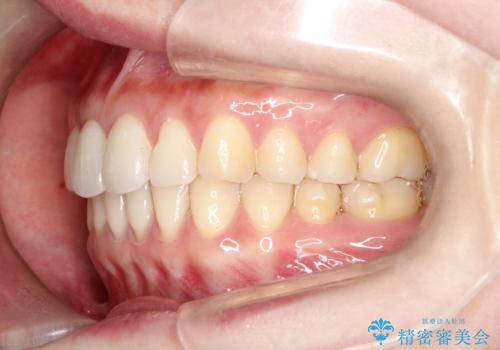

見た目、嚙み合わせ及び、治療期間や施術内容に大変ご満足いただきました。

- 前歯の見た目の改善を希望され来院された患者様です。

前歯の捻じれを改善するためにスペースを作る必要があり、前歯の歯の間を削って簡単に直す方法もありますが、奥歯のズレが認められたため、大臼歯後方のスペースを利用し、根本的な原因からしっかりと治療を行いました。